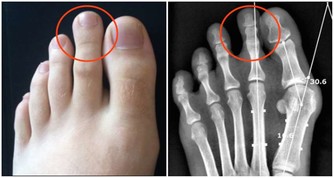

公,指的就是公共場合,所謂的公共場合包括,公用的廁所、公用的筷子、餐具,在使用公用廁所時,要養成洗手習慣,且是仔細的清洗雙手,不要在沒洗手的情況下,接觸口鼻,要知道幽門螺桿菌的感染途徑中,就有糞-口,便後洗手很有必要。